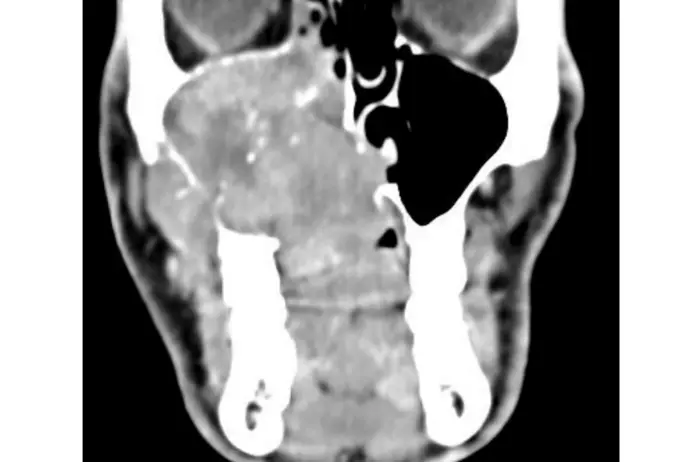

Treatment strategies for adenoid cystic carcinoma of the head and